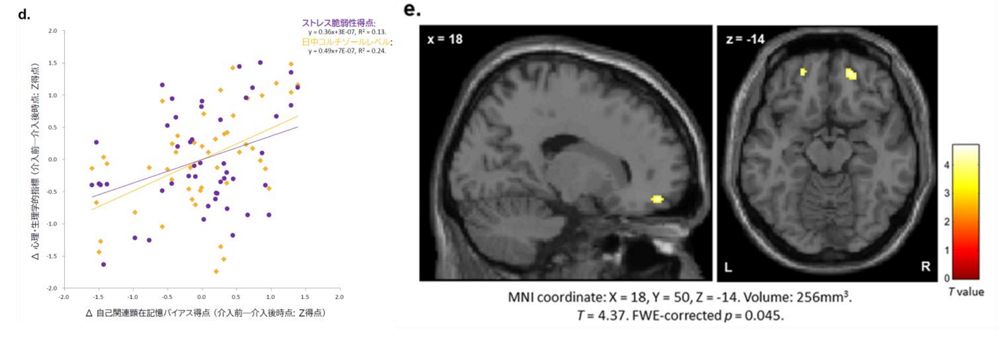

実験の実施前後で、脳のMRI検査と、ストレスホルモンとして知られるコルチゾールの量の測定を行ったところ、ストレスの影響を受けやすい「ストレス脆弱性」と、覚えた単語のうちネガティブなほうを思い出す傾向を示す「顕在記憶バイアス」が明らかな低下し、コルチゾールの分泌量も大幅に減っていた。これら2つには相関関係も見られた。

また、不安などの情動を処理する脳の右扁桃体と、心地よさの評価を行う内側眼窩前頭皮質の間の機能結合が増加していることもわかった。つまり、不安と「いいこと」の偏りのない評価が可能になったわけだ。